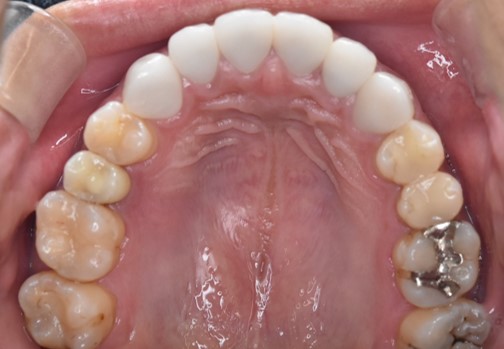

今回は抜歯後の骨の状態を踏まえ、長期的に安定するよう段階的な治療計画を立てました。骨の治癒を十分に待つことで、インプラントがしっかりと定着する環境を整えています。

インプラント症例(20代男性)左上奥歯の治療後。隣の歯を削らず補綴した状態

インプラント症例(20代男性)左上奥歯の術前口腔内写真。違和感と痛みがあったケース

After

上部構造(最終補綴物)装着

最終的な人工歯を装着し、噛み合わせを丁寧に調整して治療完了です。色・形・噛み心地を確認しながら仕上げ、周囲の歯と自然に馴染む見た目を実現しました。